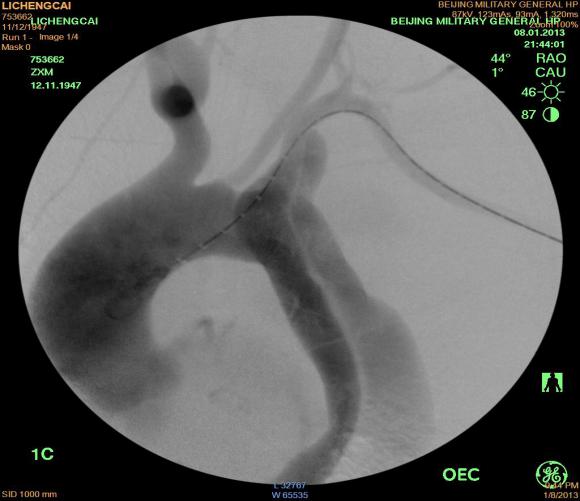

确诊主动脉夹层的主要辅助检查手段是:CT血管造影(CTA),磁共振检查(MRA)或是直接的数字剪影血管造影(DSA)。

左图为治疗前,右图植入支架后